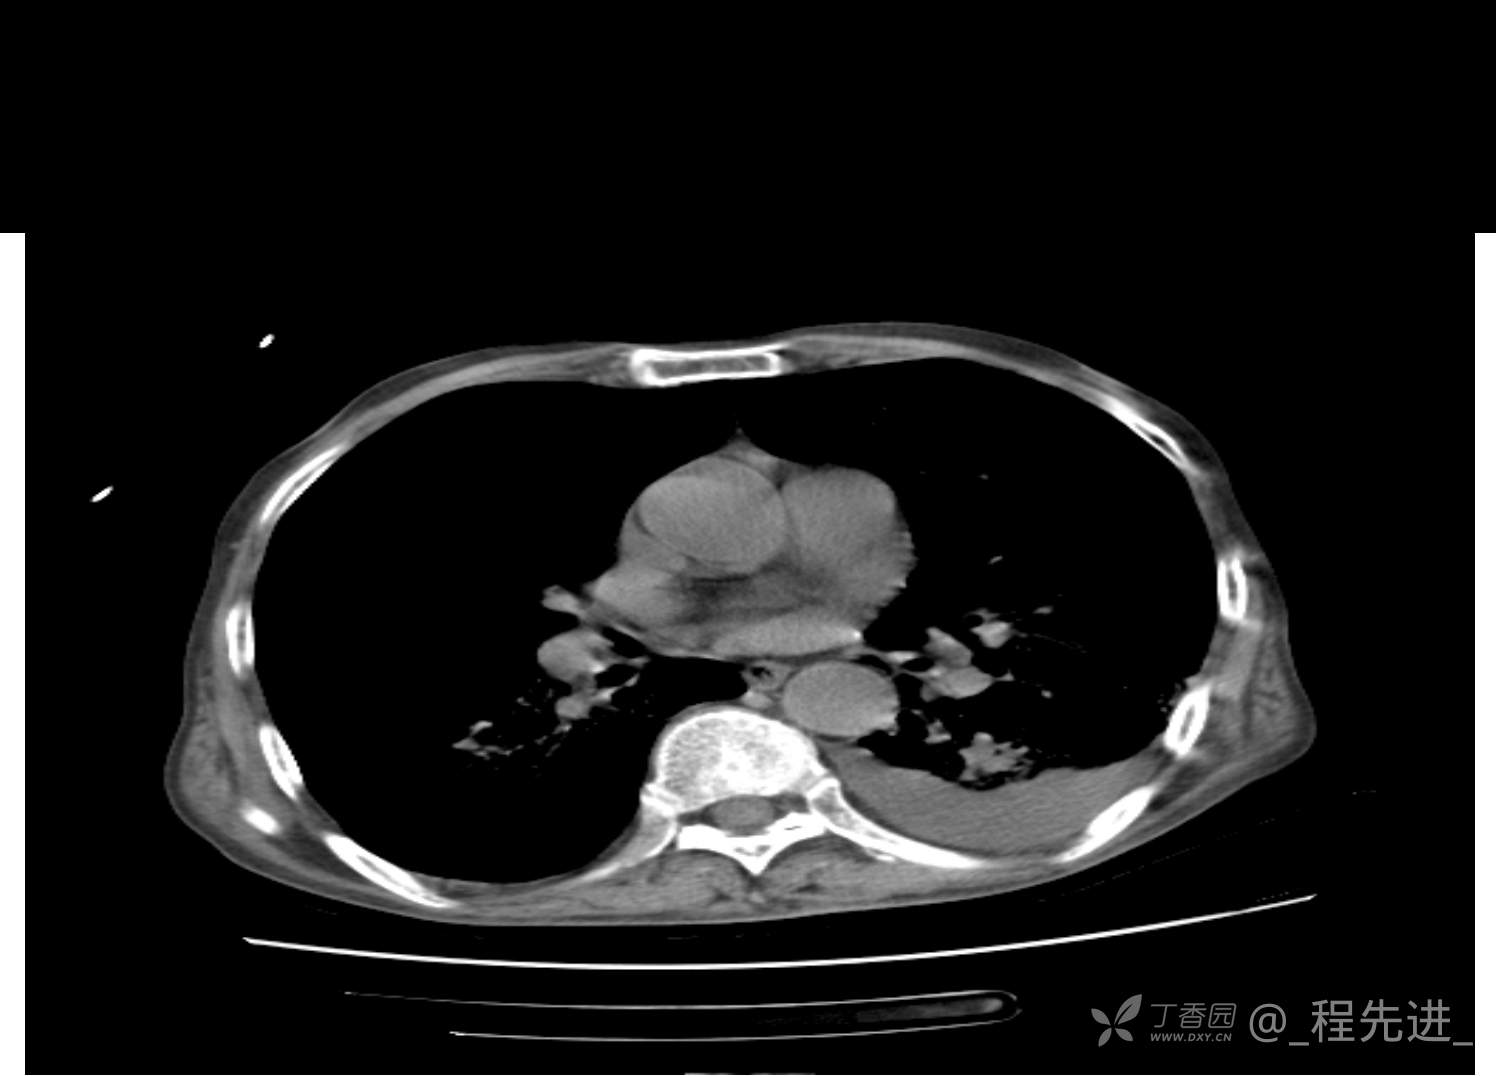

患者性别:男

患者年龄:81岁

简要病史:反复咳嗽、咳痰20余年,加重1周。两肺呼吸音低,可闻及散在干湿啰音。